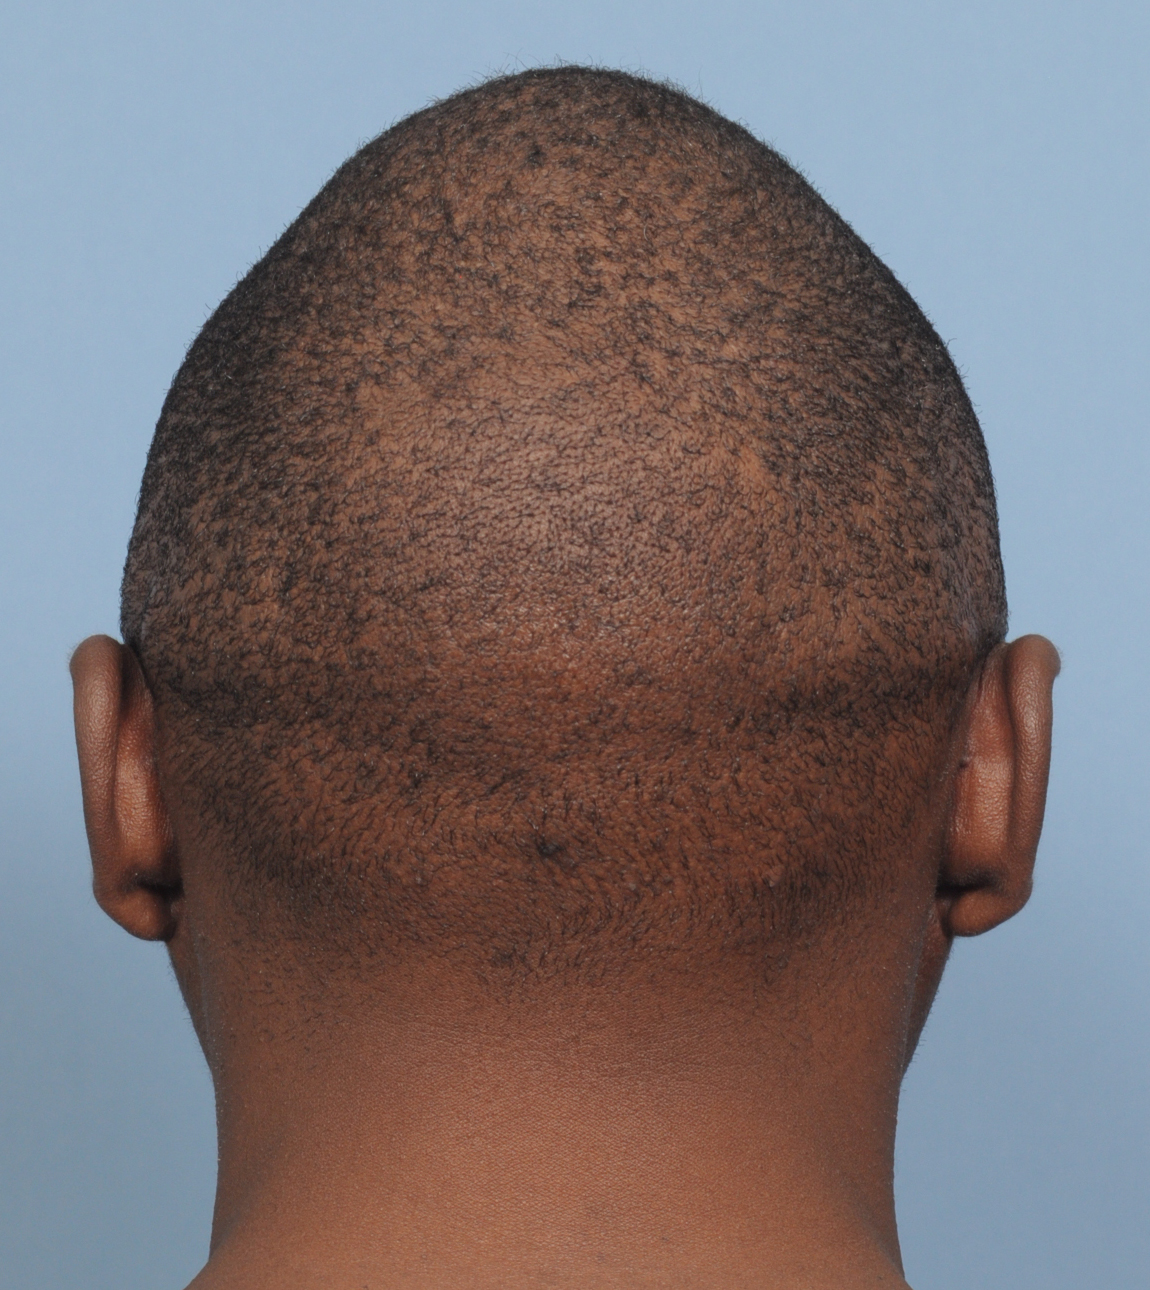

Desire for reshaping of an asymmetric flat back of the head in a shaved head male.

A combined back of the head reshaping procedure was done with a custom skull implant, sagittal ridge reduction and a right temporal muscle reduction.

Desire for reshaping of an asymmetric flat back of the head in a shaved head male.

A combined back of the head reshaping procedure was done with a custom skull implant, sagittal ridge reduction and a right temporal muscle reduction.